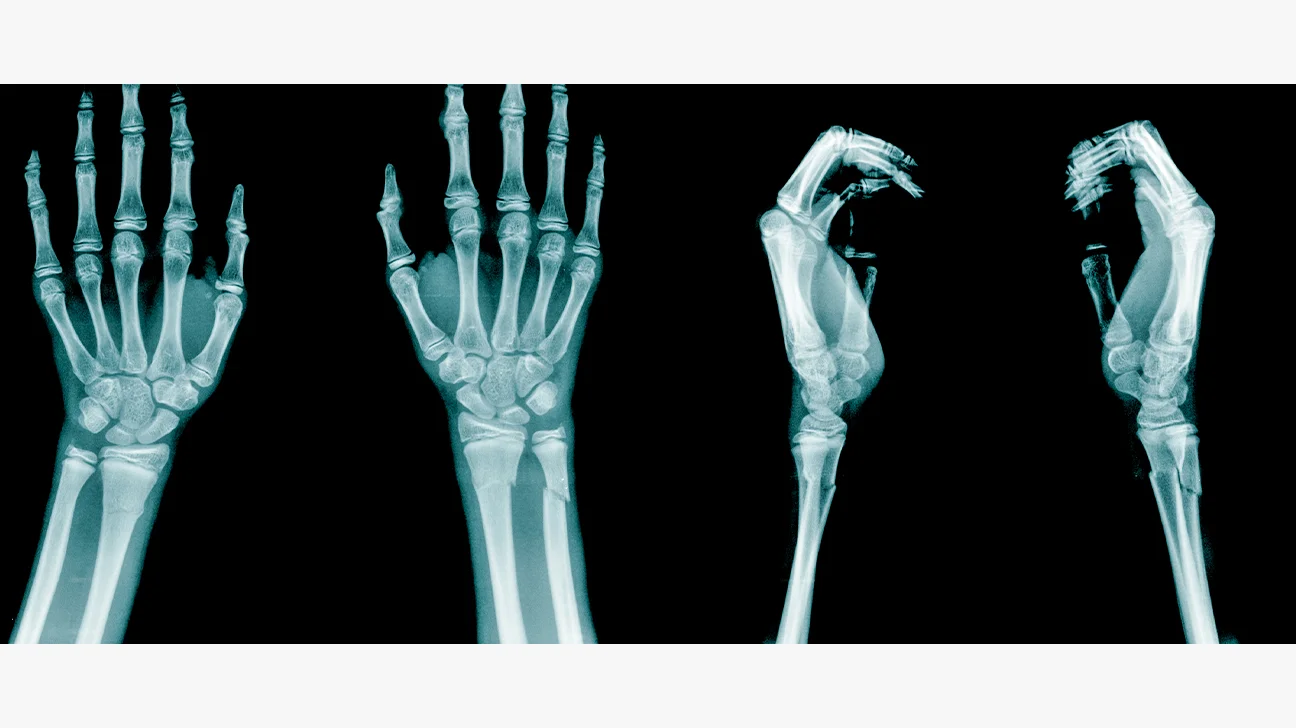

Vi åkte först till Nacka sjukhus för där vet jag att de har en röntgen, och jag såg att armen var av så jag visste ju att de skulle röntga hans handled. Men när vi kom dit hade deras röntgen precis stängt, och det enda sjukhuset som kunde hjälpa oss nu var Karolinska barnakuten så vi blev skickade dit istället. Och där var det ju väldigt många före oss i kön kan man säga, vi fick vänta i nästan två timmar på att få armen röntgad. Därefter fick vi vänta i ytterligare fem timmar innan de kunde konstatera att handleden var bruten, och att de inte kunde göra något åt saken för det fanns ej någon ledig läkartid att justera frakturen. Jag blev så arg…

Nu fick vi skynda oss hem för snart skulle Freja och Nova till skolan, så vi plockade snabbt upp dem hemma och sedan skyndade vi oss genom morgontrafiken. Vi hann fram precis i tid och kunde lämna dem där, sedan kunde Theo och jag åka hem och vila upp oss. Han hade ju så ont att han inte kunde somna på akuten, men slumrade ändå till under två timmar ungefär och jag hade inte sovit på över ett dygn när vi äntligen kom hem. Så vi lade oss på soffan och mobiltelefonen låg bredvid mig så att jag skulle höra när sjukhuset ringde, men det kom inget samtal under hela måndagen. Inte förrän på tisdag eftermiddag hörde de av sig, då hade de lyckats hitta en lucka för Theo nästa dag så på onsdagen fick vi komma tillbaka och justera armen.

Sedan fick han gå tillbaka till röntgen för att ta nya bilder så att läkaren kunde se att allt blivit rätt justerat, och det hade det så efter någon timme fick vi åka hem igen. Nu kunde han röra fingrarna och mådde betydligt bättre, det gjorde inte lika ont heller men lite Alvedon behövde han fortsätta att ta i några dagar tills allt kändes bra igen. Och nu fick han vitt gips som man kan rita och skriva på, så det har vi ordnat. Nu ska han tillbaka på fredag och ta nya röntgenbilder, om allt ser fortsatt bra ut så kommer han inte behöva operera sig och det hoppas vi att han slipper. Så nu får han ta det lugnt och inte belasta sin arm tillsvidare, så det blir förmodligen en hel del TV-serier nu för hans del. Eftersom det var hans höger handled som brutits så kan han inte göra så mycket, annat än att träna upp sin vänsterhand en del men att spela datorspel och annat blir svårt tills allt har läkt klart.